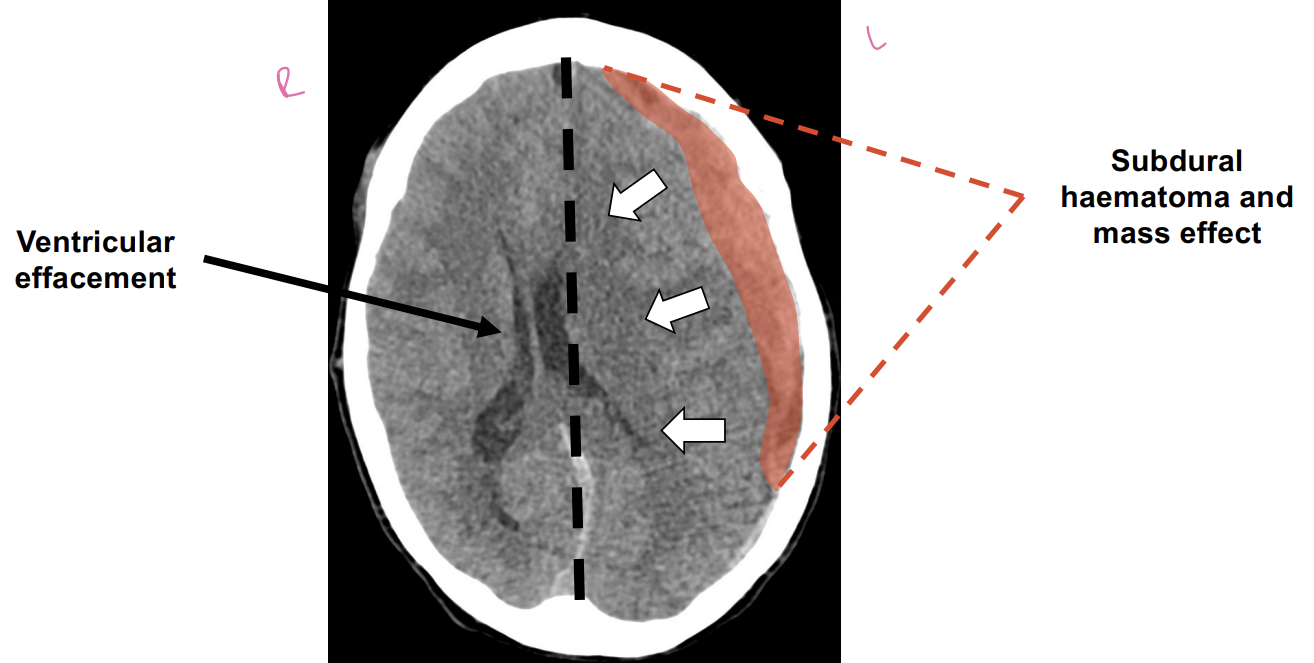

Describe the 2 types if haemorrhagic strokes

Subarachnoid haemorrhage: blood between the arachnoid membrane and pita mater

Subdural haematoma: blood between dura and arachnoid layers

Describe a craniostomy

Holes are drilled into the skull to drain haematoma and reduce intracranial pressure